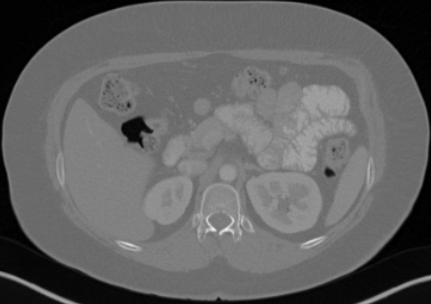

5.2 Qualitative evaluation

Fig. 2 demonstrates the L3 segmentation results and their corresponding body composition metrics (muscle density, VAT/SAT ratio, muscle area/volume, and SMI) for five selected patients. These examples were carefully selected to reflect extreme variations in body composition within the Demographic Analysis dataset, including exceptionally low and high values of muscle density (Patient 3 and Patient 2, respectively), VAT/SAT ratio (Patient 2/5 and Patient 4), muscle area (Patient 1 and Patient 2), and SMI (Patient 1 and Patient 5).

5.4 Corner Cases

In this section, we analyze the corner cases of our model to further provide insights for user application and future improvement. The corner cases include four slices carefully selected from the worst-performing volumes—two from the internal test set and two from the SAROS dataset—representing common scenarios where the model fails. As shown in Fig. 4, the model demonstrates relatively poor performance when CT images contain clear noise, as seen in the first, third, and fourth rows. This becomes more evident when zooming into the images provided in the figure’s second column. Artifacts caused by motion can also lead to model failure, as shown in the second row. The selected examples in Fig. 4 also highlight several common types of mistakes made by the model—for example, misclassifying VAT as SAT in the second row, misclassifying thick skin as muscle in the third row, and misclassifying organs as muscle shown in the forth row.